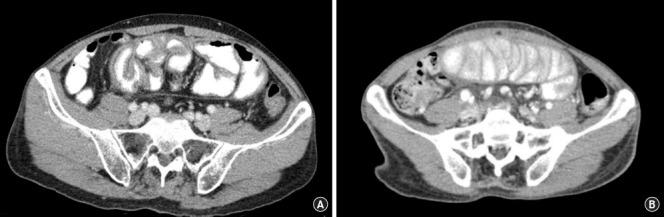

Sclerosing encapsulating peritonitis (SEP) is a rare but serious condition characterized by the progressive formation of a dense fibrous sheath encasing the small bowel within the peritoneal cavity. This review provides a comprehensive overview of the current understanding of SEP, focusing on its etiology, clinical presentation, diagnostic modalities, and management strategies. SEP can be classified into primary and secondary forms, each with distinct etiologies and treatment approaches. Primary SEP typically presents with acute or subacute bowel obstruction symptoms, necessitating surgical intervention to excise the fibrous sheath and relieve the obstruction. Secondary SEP often occurs in patients undergoing peritoneal dialysis, with cessation of dialysis being a key component of management. Medical treatments, including corticosteroids, immunosuppressive agents, and nutritional support, may complement surgical intervention, particularly in cases of secondary SEP. Advanced imaging techniques and personalized medicine approaches show promise in improving diagnostic accuracy and tailoring treatment strategies to individual patients. Future research directions include investigating targeted pharmacological therapies, exploring minimally invasive surgical techniques, and conducting long-term follow-up studies to evaluate treatment efficacy and disease recurrence. Multidisciplinary care teams play a crucial role in the comprehensive management of SEP, emphasizing collaboration among various specialties to optimize patient outcomes.